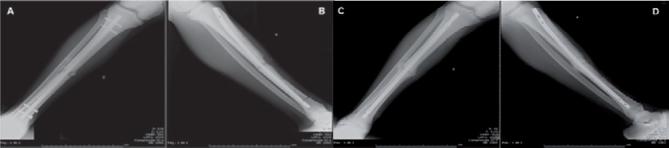

To compare efficiency of external fixator in modular form with unilateral and uniplanar intramedullary locked seeking definitive treatment of fractures of the tibia diaphysis.

Orthopedic surgical treatments were compared to 50 patients with definite diafisaria fracture of the tibia, through the use of the external fixator, modular and intramedullary locked. The fractures were treated at emergency hospital school of External fixators Orthopedics and Traumatology service in the period from January 2007 to January 2011, Locked Intramedullary Nail with a variation of 15 to 48 weeks.

this study has proven functional results and Tibial fractures/therapy excellent consolidation when locked intramedullary rods were used and the versatility and speed of application of external fixator reaching the necessary stabilization of bony fragments. Consolidation of fractures was obtained in 95 cases when using the intramedullary locked and 90 cases undergoing external fixation.

the definitive treatment of tibial diaphysis fractures by external fixator modular presented themselves as valid alternative treatment in patients who could not be submitted for early conversion to internal osteosynthesis or when the intramedullary nails are not available to the surgeon.